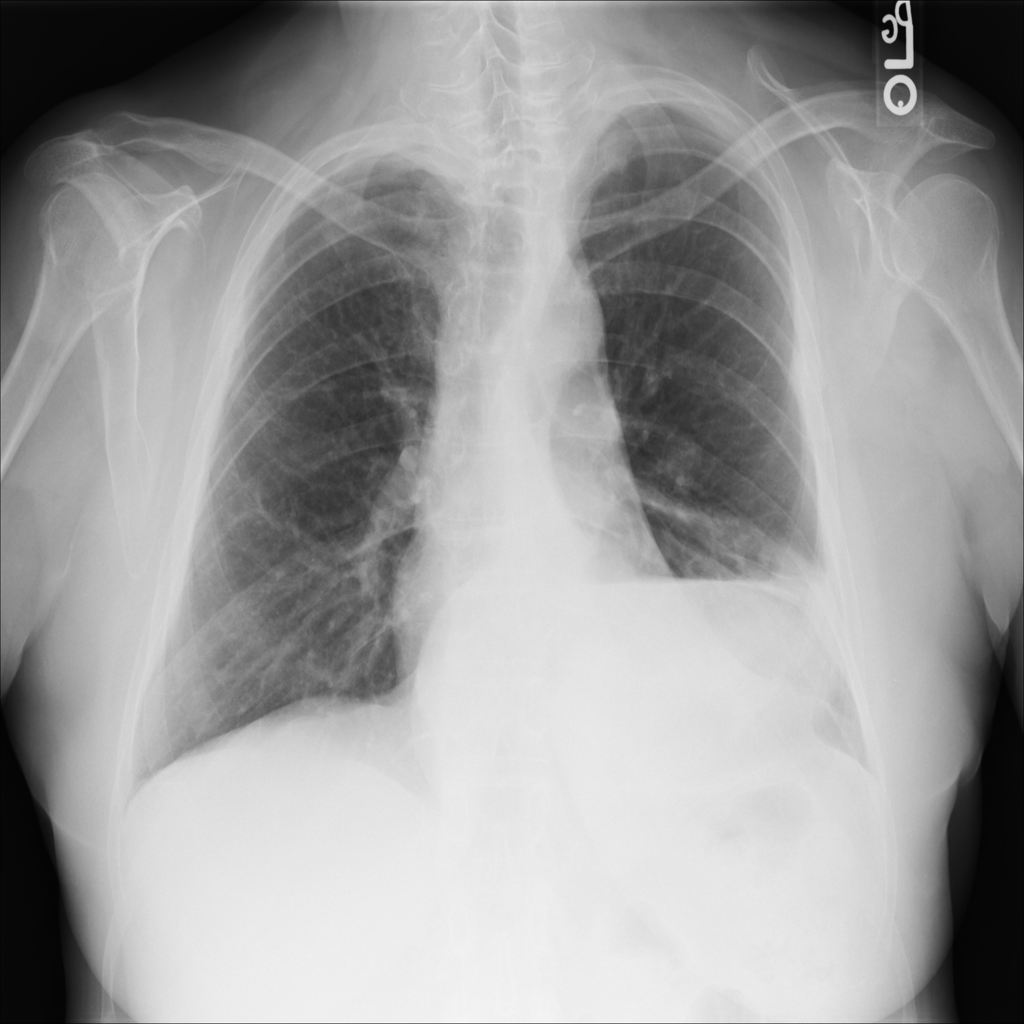

PAT-0ABD · IMG-000Hernia

PAT-0ABD · IMG-000

PA